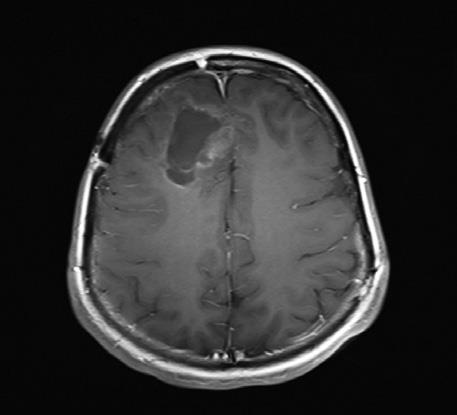

Сейчас проходят и вовсе поразительные клинические испытания. Ученые из Университета Дьюка используют другую иммунную стратегию, модифицируя вирус полиомиелита. Идее борьбы с раком с помощью вирусов больше ста лет, но необходимые для экспериментов технологии и технические новинки появились сравнительно недавно. Последний случай заражения полиомиелитом случился в США в 1979 году. Ученые Университета Дьюка заметили одно интересное свойство вируса: он убивает клетки, попадая в них через «дверь»-рецептор. Как оказалось, рецептор для вируса полиомиелита присутствует на большинстве клеток твердых опухолей – раков легких, груди, мозга, простаты, – а вот на большинстве нормальных клеток отсутствует. Проблема лишь в том, что вирус может прикрепляться еще и к клеткам нервной системы – нейронам. Когда вирус убивает их, это приводит к мышечному параличу. Если удалить болезнетворную часть вируса, заражающую нормальные нейроны, и подменить ее безвредным вирусом простуды, а ту часть, что прикрепляется к раковым клеткам и уничтожает их, оставить, то мы получим безопасный вирус. Вирус впрыскивается прямо в опухоль, заражает несколько раковых клеток и убивает их, в то же время активизируя иммунную систему. Она просыпается: «Эй, это же полиомиелит!» – и вместе с вирусом убивает еще и «ни в чем не повинные» клетки опухоли. Вирус, по сути, помечает опухоль как «чужеродный предмет» и заставляет иммунную систему тела идти в бой. Исследования с вирусом полиомиелита на данный момент ведутся в основном на пациентах с продвинутой стадией глиобластомы – одного из самых смертоносных и агрессивных видов рака мозга, который часто убивает через несколько недель после того, как все стандартные способы лечения перестают работать. Ученым удалось продлить жизнь нескольких пациентов на месяцы и даже годы [9]. ![]() ![]() ![]() Энцефалограммы 20-летнего студента, которого лечат модифицированным вирусом полиомиелита (PVS-RIPO), вводимым через катетер, подсоединенный прямо к опухоли. Слева – опухоль до лечения (затененная область в верхней левой части мозга). В середине – опухоль после двух месяцев лечения (она кажется даже больше из-за воспаления, вызванного иммунным ответом). Справа – опухоль, уменьшившаяся после девяти месяцев лечения. Идея использования собственной иммунной системы для лечения рака, конечно, романтична, но и в ней есть свои опасности. Наша иммунная система, если ей позволить работать на полную мощность, очень сильна. Спускать ее с тормозов, даже в надежде, что она может убить дьявольские, сошедшие с ума клетки, очень рискованно. Некоторые пациенты, попробовавшие иммунотерапию, умерли от тяжелейших осложнений, вызванных неудержимой иммунной системой, которая вместе с раком начала атаковать здоровые, жизненно необходимые ткани и органы. С помощью клинических испытаний ученые надеются преодолеть эту трудность. Иммунотерапия – важное оружие против рака и останется таковым и в дальнейшем, но сейчас она подходит лишь для определенных видов рака и только некоторых пациентов. Главная трудность – заранее определить, кому она подойдет. Кроме того, нужно лучше понять, какое сочетание «checkpoint ингибиторов» или других препаратов лучше всего помогает иммунной системе бороться с раком. На самом деле, чем больше мутирует рак, тем легче с ним бороться с помощью иммунотерапии, потому что его клетки становятся все более «инородными на вид» для организма. Иными словами, чем ненормальнее становится опухоль, тем труднее ей избегать обнаружения со стороны иммунной системы, особенно после того, как лекарственная терапия уже приводит ее в состояние постоянной готовности и оснащает специальными «очками ночного видения». Это явление было недавно описано в выдающейся статье в New England Journal of Medicine командой исследователей из Онкоцентра имени Сидни Киммела в Университете Джонса Хопкинса [10]. ДНК в теле постоянно ремонтируется с помощью инструментов для «репарации ошибочно спаренных нуклеотидов». Эта группа исследователей обратила внимание на гены репарации ошибочно спаренных нуклеотидов, которые кодируют систему, используемую телом для распознавания и ремонта испорченной ДНК, они либо присутствуют, либо нет. Выяснили, что вне зависимости от типа рака опухоли, у которых эта система не работает, с большей вероятностью реагируют на лекарство, блокирующее PD-1 и снимающее с тормозов иммунную систему, чем те, у которых репарация работает нормально. Иными словами, чем хуже клетки опухоли умеют ремонтировать ДНК, тем лучше пациенту помогает лечение. Иммунотерапия, скорее всего, не сможет лечить рак в одиночку: ее будут использовать в сочетании с другими методами, в том числе химиотерапией, радиационной терапией и молекулярно-таргетированными лекарствами. Тем не менее она станет незаменимым инструментом, который будет даже еще сильнее благодаря дополнительному «оружию». Некоторые пациенты, проходившие иммунотерапию, умерли от осложнений, вызванных неудержимой иммунной системой, которая вместе с раком начала атаковать здоровые, жизненно необходимые ткани и органы. Одно из удивительных открытий, связанных с иммунотерапией, состоит в том, что многие люди, которые ее попробовали, говорили, что чувствуют себя лучше, несмотря на то что рак никуда не делся и даже в некоторых случаях рос. Но это проблема моей специальности. Единственный измеримый параметр успеха – уменьшение опухоли. Замедление ее роста, улучшение самочувствия или продление жизни дальше ожидаемого срока в онкологии обычно не считается «успехом». Если вы придете ко мне с 5-сантиметровой раковой опухолью, я пропишу вам лечение, и через несколько месяцев ваша опухоль увеличится до 7 сантиметров, подействовало ли лечение? Может быть, без лечения опухоль была бы уже размером 15 сантиметров? По большей части, пробуя новые лекарства, замедляющие или останавливающие рак, и врачи, и пациенты двигаются на ощупь. В любом рандомизированном клиническом испытании лекарство, возможно, поможет группе пациентов в целом прожить дольше, но очень трудно определить, что оно делает в каждом конкретном случае. Если вы, например, сможете спокойно прожить два года, принимая лекарство X, не все ли вам равно, насколько у вас большая опухоль, если побочные эффекты вполне терпимы, а чувствуете вы себя хорошо? Ни один пациент мне еще не говорил чего-либо вроде «Лучше бы я умер в прошлом году». Даже самые больные пациенты не жалеют, что прожили дольше, чем ожидалось. Они готовы практически на все, чтобы прожить один лишний день, и часто готовы на любые, даже самые абсурдные с виду эксперименты. Проще говоря, они готовы идти на риск вместе со мной в нашей общей доблестной битве. |